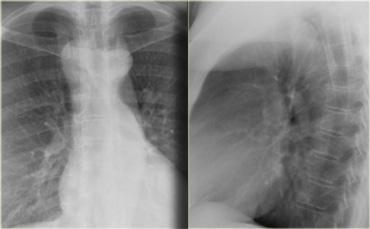

On the left a chest film of a 6-month old boy with stridor and cough.

The trachea is deviated to the left, otherwise the chest film is normal.

So there is some mass effect on the right side.

On the left the reconstructions demonstrating a double aortic arch.

There are branches coming off the right arch and branches coming off the left arch.

The right arch is typically larger and higher than the left.

There is a complete ring that encircles the esophagus and the trachea and usually there is stridor or dysphagia.

Two brachiocephalic arteries arise on each side separately (four vessel sign).

On the left a chest film of a young adult with a cough.

There is a right paratracheal mass.

The differential diagnosis is tumor, adenopathy or vessel (right arch, dilated azygos vein, dilated aberrant right subclavian artery).

On the left axial images and posterior view of volume rendered reconstruction.

The findings are:

- four vessel sign

- double arch

- right arch higher and larger

- esophagus and trachea are completely encircled

The narrowing of the trachea is seen on the axial images, but better appreciated on the MPR and Volume Rendered image.

On the left preoperative and postoperative MDCT studies of a 2-month-old female infant with double aortic arch presenting with stridor and repeated apnea.

The smaller left arch is partially resected.